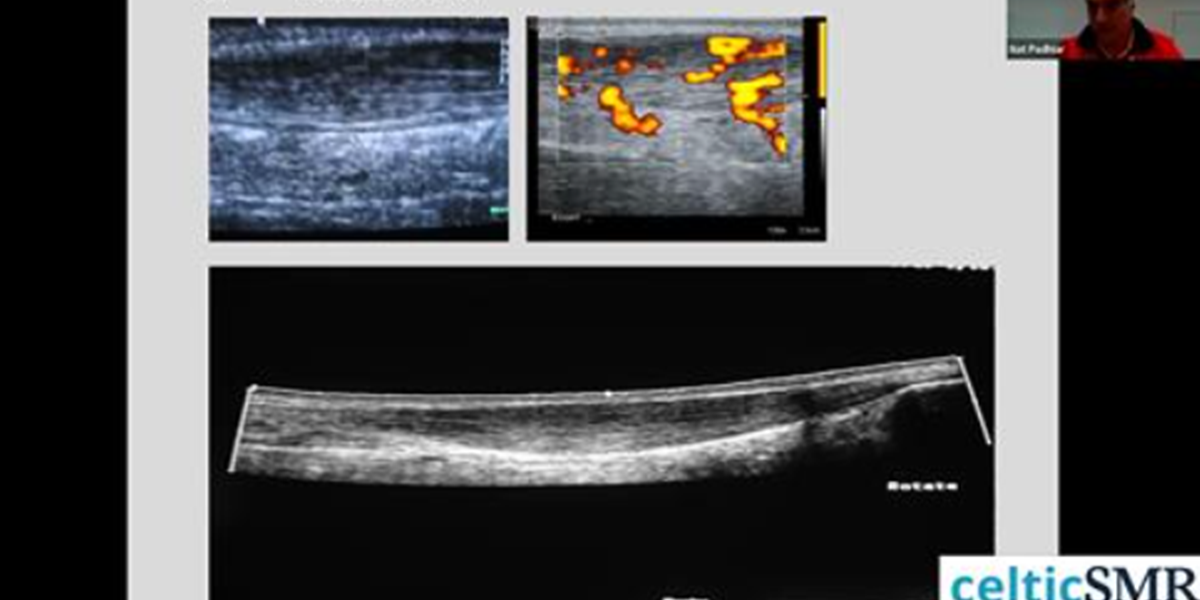

Prof. Nat Padhiar - MSK clinicians stethoscope and guidance system

Catch up here on last weeks webinar with Prof. Nat Padhiar - MSK clinicians stethoscope and guidance system...well worth a watch: